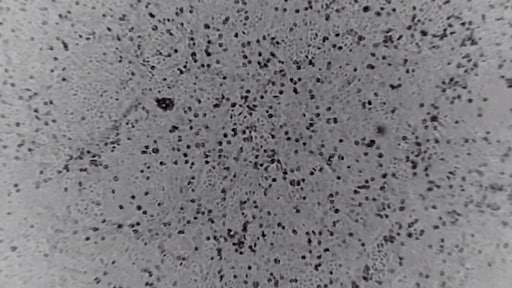

Een 'game changer', noemt het Australische Peter Doherty Institute hun ontdekking. Ze hebben een kopie weten te maken van het coronavirus op basis van een monster van een patiënt.